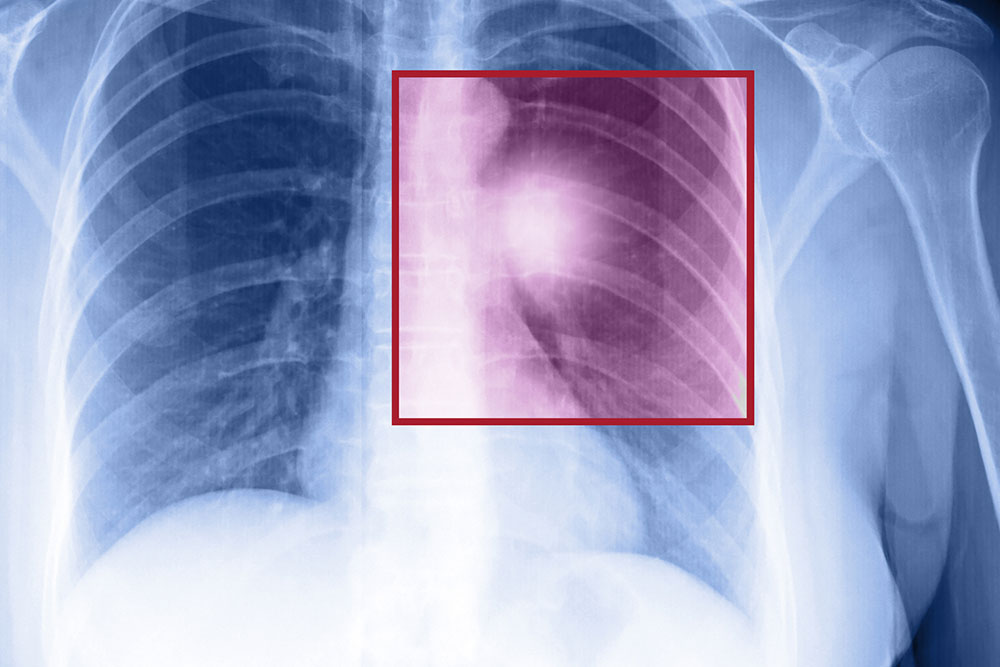

• Chest X-ray which provides detailed images of the lungs.